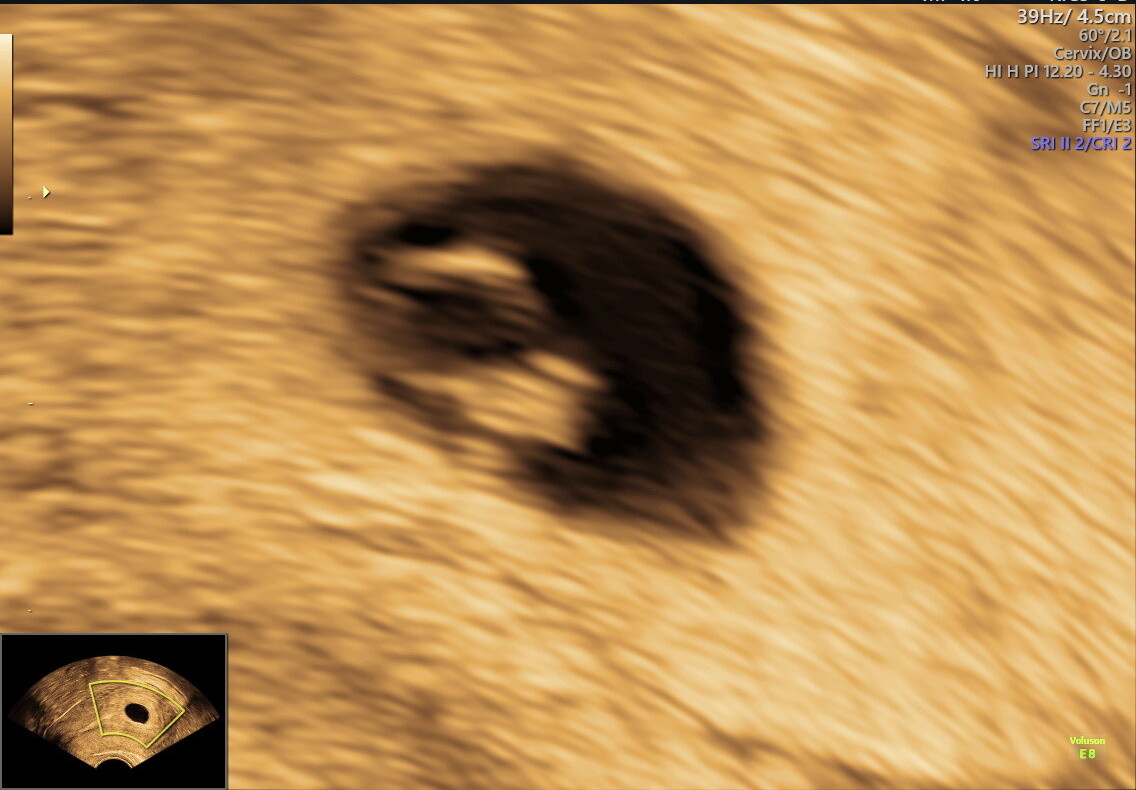

Det er jo veldig forskjellig fargestoff på de forskjellige testene. Det tok laaaaang tid før mine tester ble sterkere denne ganga, så jeg var overbevist om at det var tom fostersekk da jeg var på ultralyd, men jammen var det ikke en liten bamsemums med bankende hjerte.